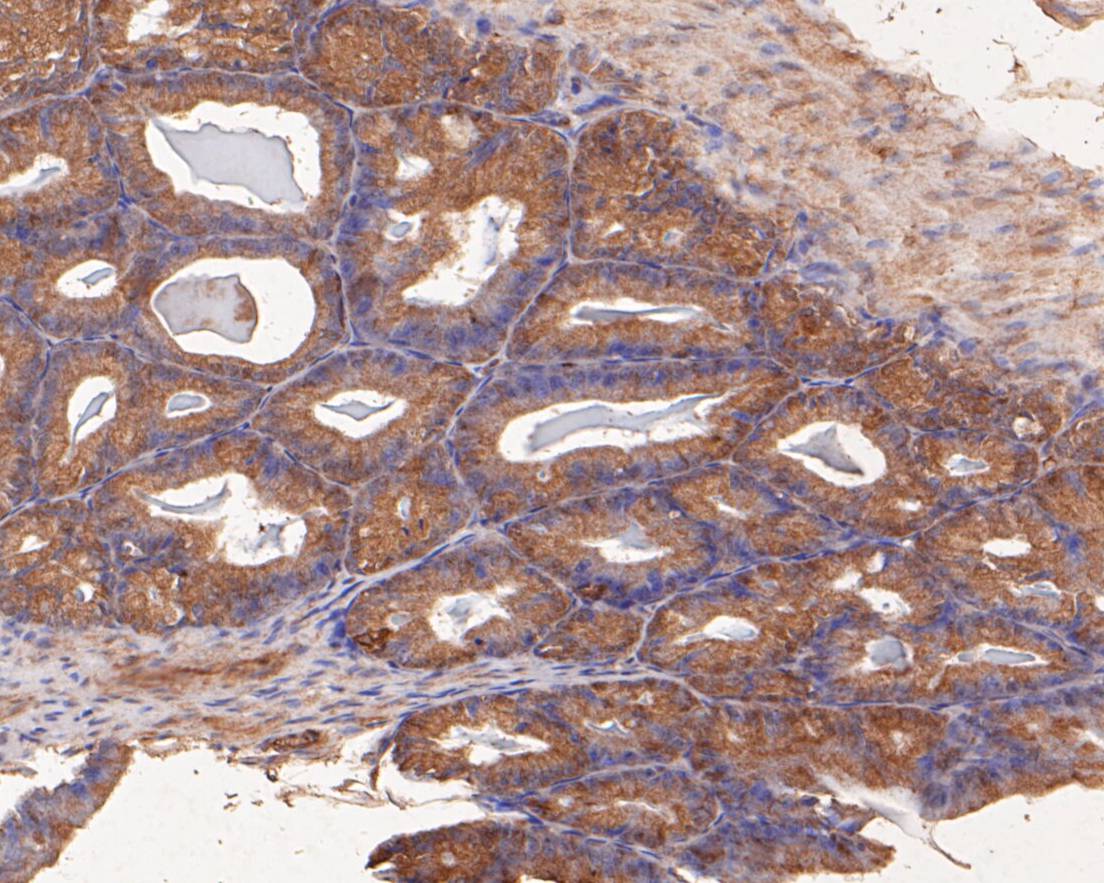

Immunohistochemical analysis of paraffin-embedded human breast carcinoma tissue using anti-SPATA5L1 antibody. The section was pre-treated using heat mediated antigen retrieval with Tris-EDTA buffer (pH 8.0-8.4) for 20 minutes.The tissues were blocked in 5% BSA for 30 minutes at room temperature, washed with ddH2O and PBS, and then probed with the primary antibody (EM1901-36, 1/50) for 30 minutes at room temperature. The detection was performed using an HRP conjugated compact polymer system. DAB was used as the chromogen. Tissues were counterstained with hematoxylin and mounted with DPX.